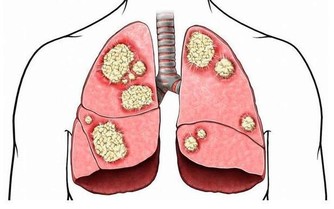

冬季是流感以及腮腺炎、扁桃體炎的高發季節,體質虛弱的人群可以在中醫的指導下合理的使用板藍根或者大青葉來預防腮腺炎或者流感,選擇魚腥草或者蘭花草來預防百日咳。另外要注意四肢以及臉和耳朵的保健,防止發生凍瘡。